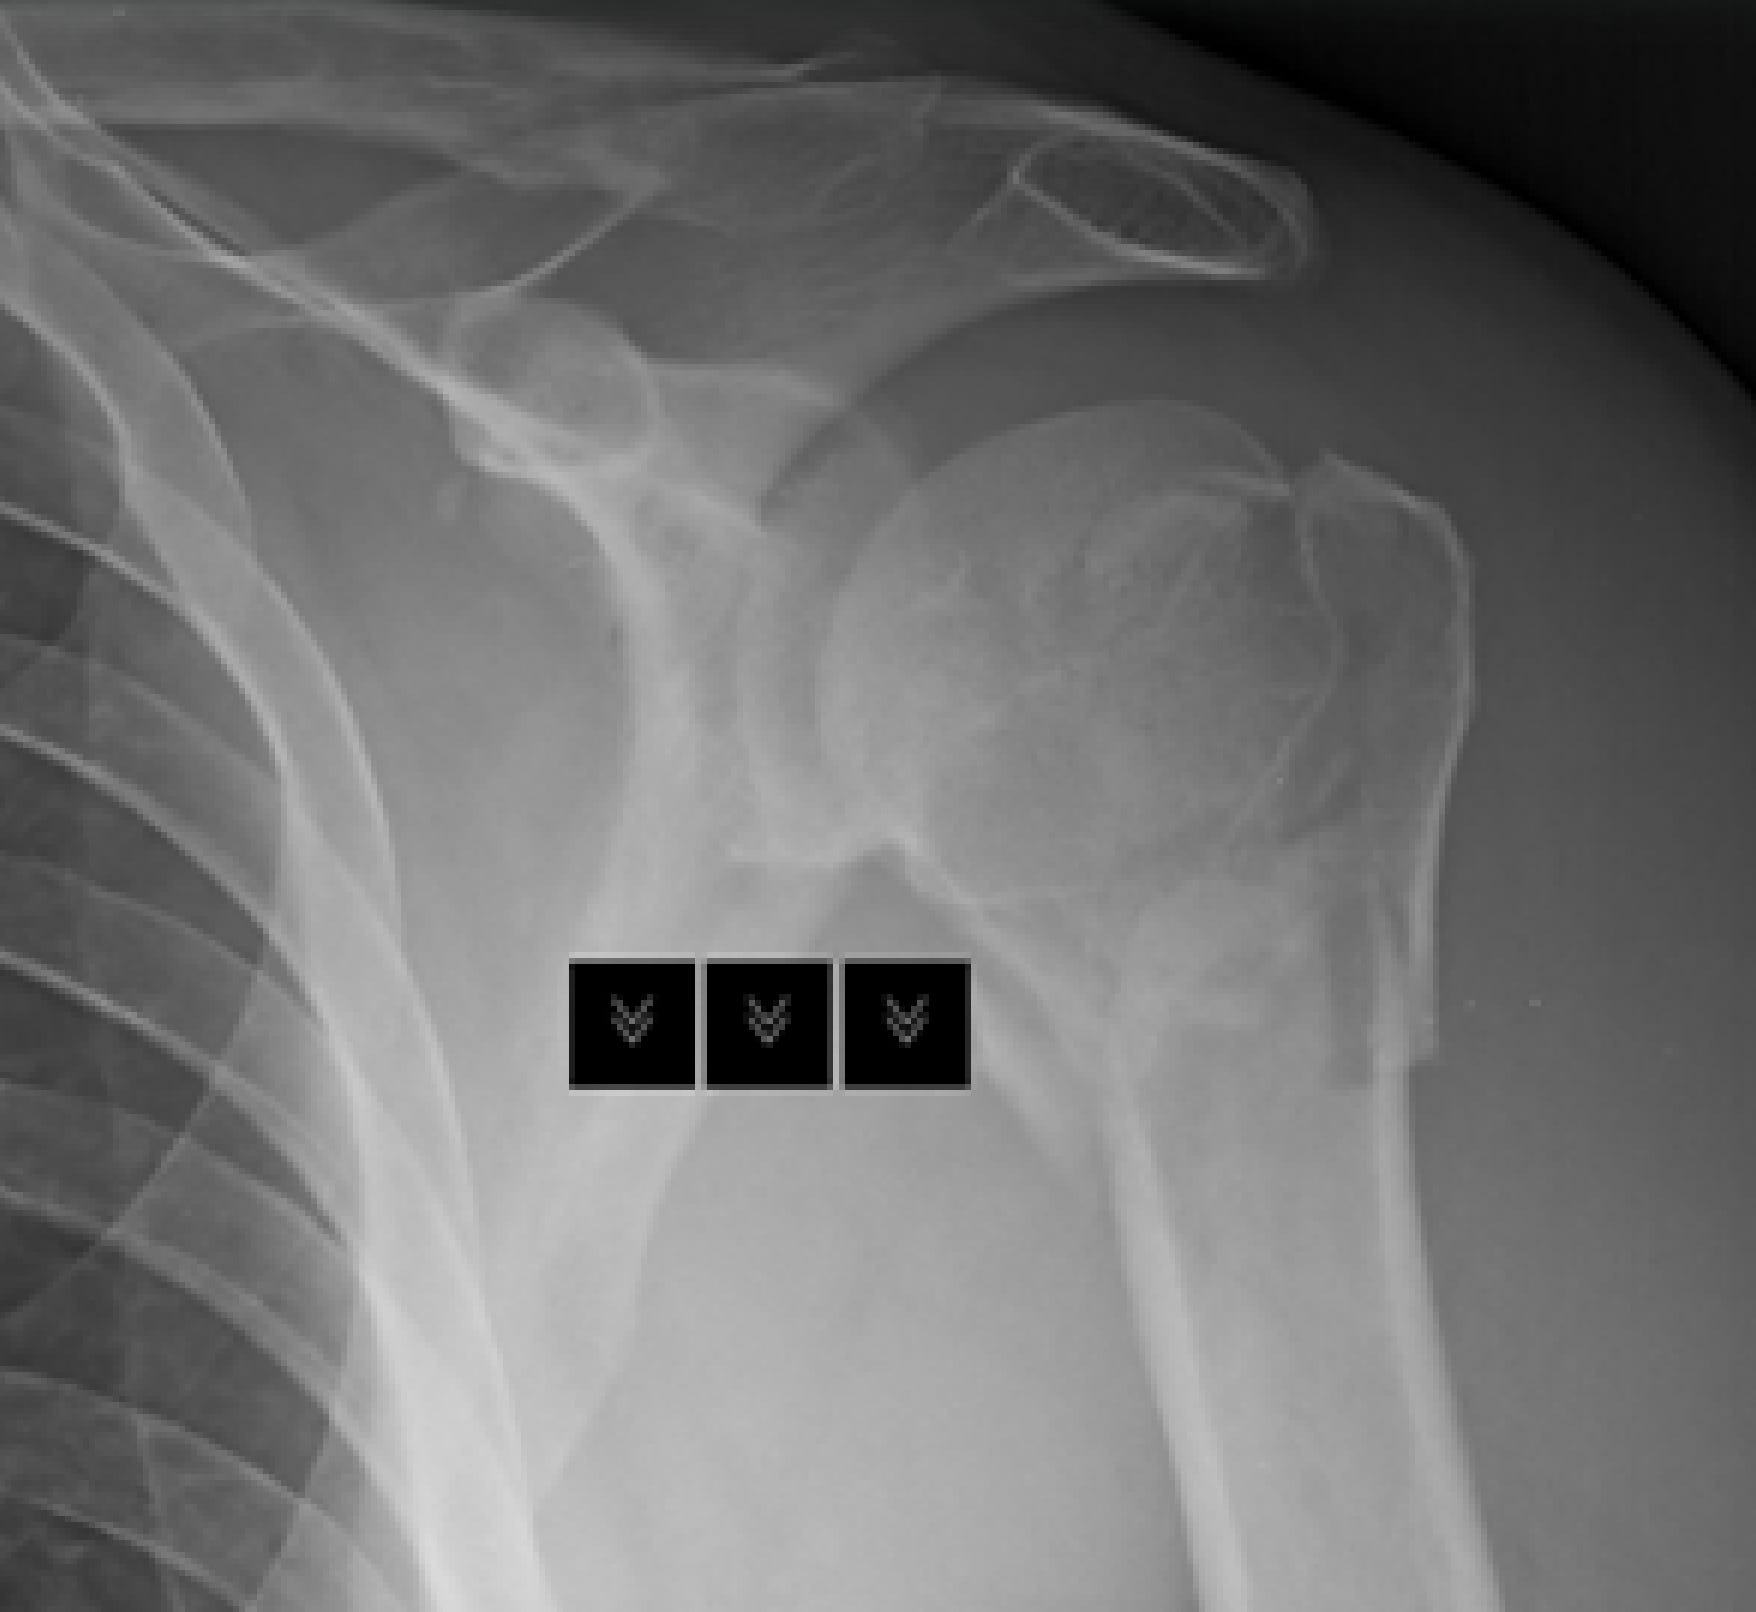

I love life and in between lazy stints on my bean bags watching trash I try to get the most out of it. I shattered my humeral head (shoulder) a bit under four weeks ago. Diving in my pool as I’d done for eight years. Entered water wrong, wrist that normally absorbs downward energy slips, elbow hit bottom, shoulder shattered.